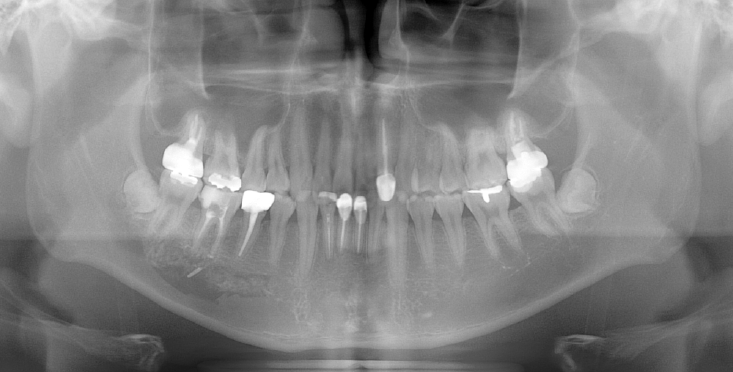

A 41-year-old female reported persistent numbness in the right lower lip and chin following endodontic treatment of the mandibular right second molar (#47). A panoramic radiograph and CBCT revealed extrusion of Calcipex II into the IAN (Fig. 3). She declined surgical intervention and was treated conservatively with mecobalamin and gabapentin. Serial follow-ups at one and three months showed no clinical improvement.

A. Pre-op panoramic radiograph of Case 2 patient. B. Pre-op CBCT of Case 2 patient.